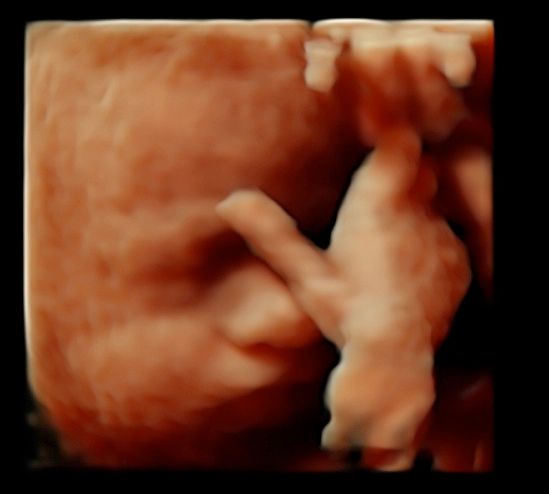

Subito dopo la laurea, il dottor Tommaso Incandela, ha conseguito l'idoneità ospedaliera nella branca di Ostetricia e Ginecologia con il giudizio finale di ottimo. Dall'Aprile 1977 fino al Gennaio 1982, su delibera del consiglio di facoltà, ha svolto la funzione di medico interno della seconda cattedra di Ostetricia e Ginecologia con mansioni didattiche, di assistenza e di cura. Dal Luglio 1981 al mese di Ottobre 1992 ha ricoperto la funzione di assistente di ruolo presso la seconda divisione di Ostetricia e Ginecologia dell'Ospedale Civico e Benfratelli di Palermo. Dal 1 Novembre 1992 fino alla fine di Giugno 1998 è stato dirigente medico del Consultorio familiare di Santa Flavia. Dal Luglio 1998 a tutt'oggi si dedica a tempo pieno all'attività libero professionale occupandosi di ecografia ostetrica e ginecologica con particolare riguardo per la diagnosi prenatale di patologie cromosomiche e malfomative (studio di aneuploidie cromosomiche su DNA fetale prelevato dal sangue materno, amniocentesi precoce, ecocardiografia fetale, ecografia morfologica e cardiotocografia) tutte queste indagini sono inserite nel monitoraggio della gravidanza. Il dottor Tommaso Incandela si occupa altresì di diagnosi precoce e terapia di patologie del tratto genitale inferiore e nel corso degli anni ha acquisito una notevolissima esperienza nell'ambito della terapia conservativa dei fibromi uterini mediante terapia farmacologica e/o inserimento di spirali medicate al progestinico. Da un punto di vista chirurgico il dottor Incandela si occupa di patologie del corpo uterino ivi compresa l'asportazione di fibromi con conservazione dell'utero stesso anche in pazienti meno giovani e con assenza di desiderio di prole. Il dottor Incandela si occupa anche di chirurgia del pavimento pelvico con particolare riguardo per la terapia dell'incontinenza urinaria, dei prolassi uterini e vescicali e delle lacerazioni antiche da parti pregressi.

• Ecocardiografia fetale

• Ecografia morfologica